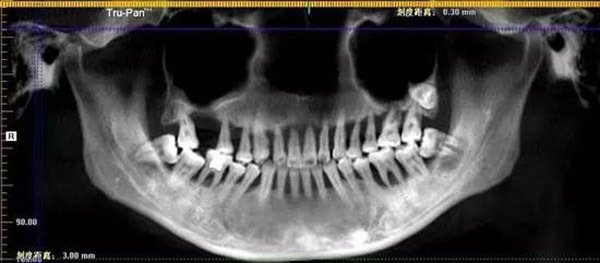

Một cô gái 28 tuổi lại có bộ răng móm mém, lỏng lẻo như một bà cụ, mất toàn bộ chức năng nhai thức ăn.